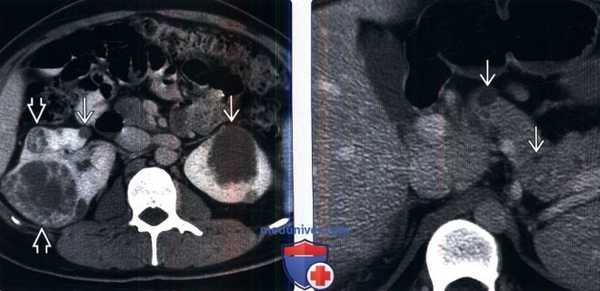

(Слева) КТ без контрастирования, аксиальная проекция: поликистозное поражение почек и печени. В то время как большинство кист почки гиподенсные, периферические кисты левой почки - гиперденсные, сравнимые по плотности с геморрагическими кистами.

(Справа) КТ без контрастирования, аксиальная проекция: у пациента с аутосомно-доминантной поликистозной болезнью почек выявлены множественные простые кисты почек и сложные кисты с пристеночными кальцификатами.в) Дифференциальная диагностика аутосомно-доминантной поликистозной болезни почек: